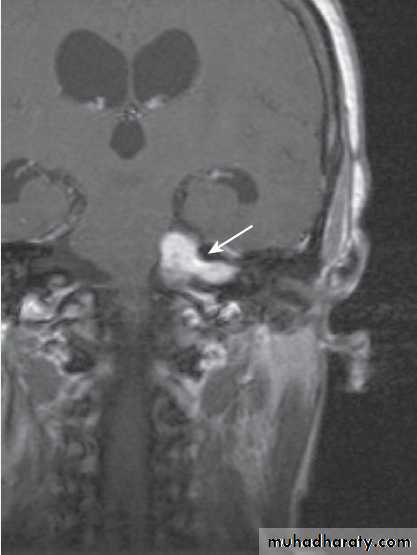

Acoustic Neur(in)oma

1-tumors(acoustic neuroma)